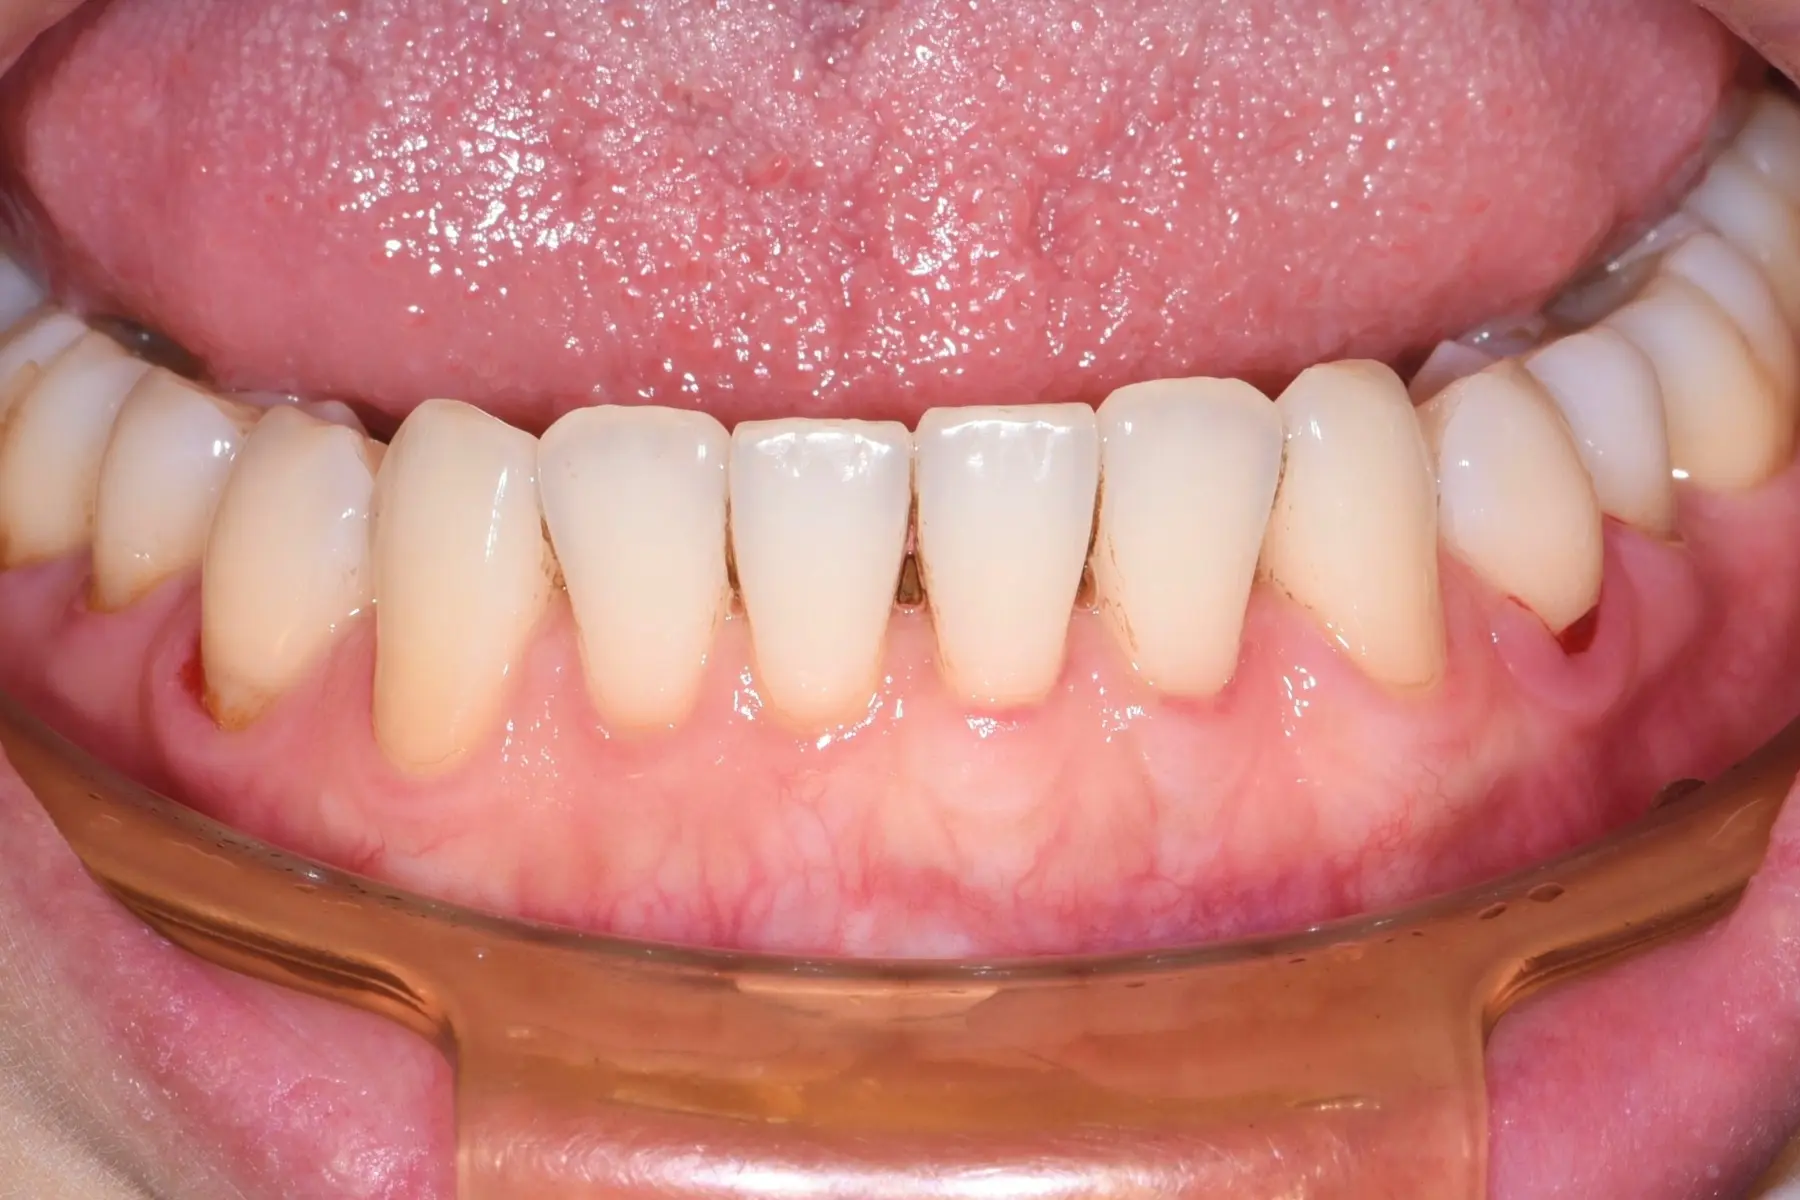

• 術前 18

術後 17

牙根覆蓋術

主治醫師

• 林明志

治療時間

單次療程

主訴

前牙牙齦萎縮露出牙根,想評估牙齦增補手術